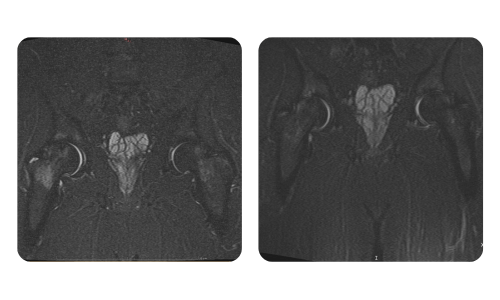

I progressi dei nostri pazienti, misurati prima e dopo la terapia iperbarica, riflettono l'efficacia e l'impatto positivo del trattamento. Scopri i risultati documentati della terapia iperbarica presso la clinica Hyperbarium Oradea, basati su valutazioni cliniche e dati oggettivi che evidenziano miglioramenti significativi in diverse condizioni.